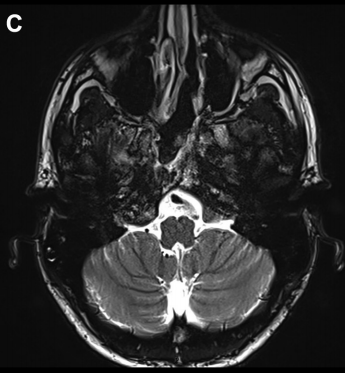

▼图2,术后MR证实软骨肉瘤完全切除。

▼术后影像学证实了肿瘤全切(图7C)和颈静脉孔保留通畅(图7D)。在这种情况下,神经内镜筷子技术有助于顺利合适地暴露、探查神经和斜坡旁颈内动脉,并通过有限且定制的手术入路向下到达对侧肿瘤所在位置颈静脉孔区域。